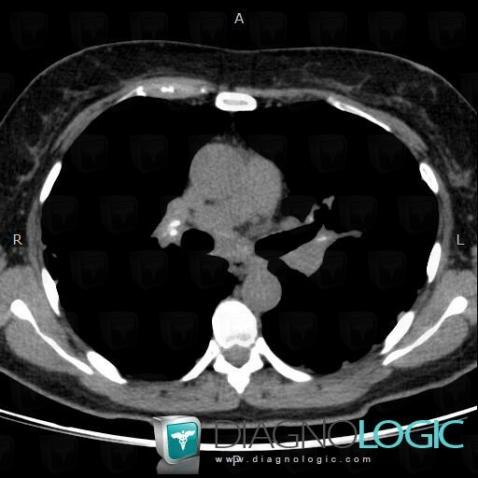

Les images ci-dessous illustrent ce dossier pour les diagnostics Sarcoïdose (lié à Fibrose pulmonaire), Sarcoïdose, pour les modalités (Scanner)

Voici les informations spécifiques à l'image clé ci dessus:

- Diagnostic Sarcoïdose, Localisation(s) Plèvre, comportant les gammes Epaississement pleural